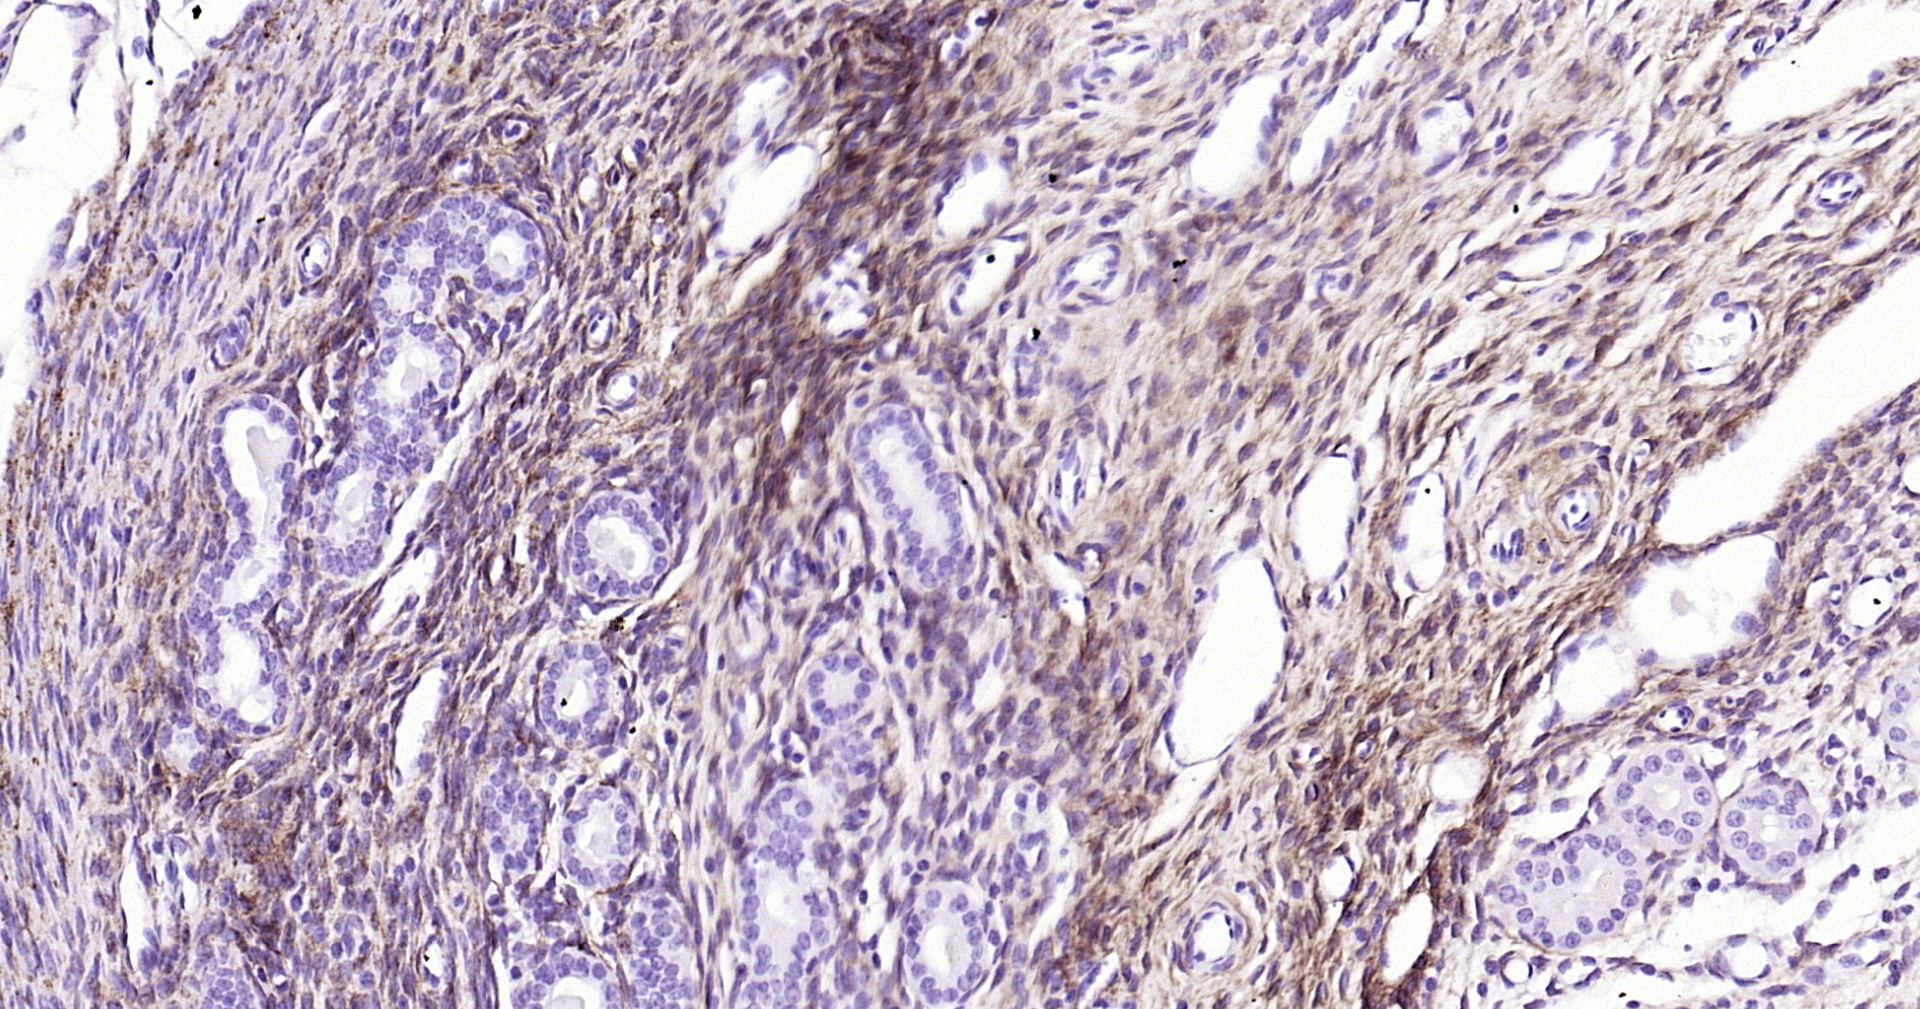

NGFR/p75NTR Recombinant Antibody

Product Name NGFR/p75NTR Recombinant Antibody

IHC-P 1:100-500